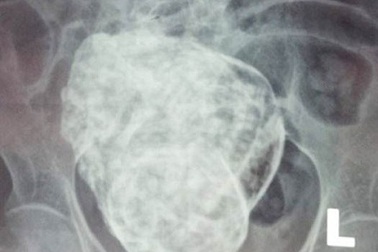

Hội chẩn liên viện trường hợp cụ bà mang “thai đá” gần 30 nămTrường hợp mang “thai đá” 30 năm của cụ Sáu dự kiến sẽ hội chẩn liên viện giữa bệnh viện Đa khoa Khánh Hòa với bệnh viện Đa khoa Khu vực Cam Ranh nhằm tìm hướng điều trị phù hợp vào ngày 31/3 này.